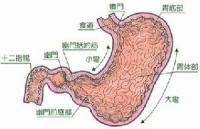

胃可分为四个部分:贲门部、胃底部、胃体部和胃窦部。胃的入口为贲门,出口为幽门。胃窦指的是幽门与胃角切迹平面之间的部分。胃窦炎好发于30岁以上的男性,表现为上腹部饱胀,隐痛或剧痛,常呈周期性发作,可伴有嗳气、反酸、呕吐、纳差、消瘦等,慢性胃窦炎还可表现为厌食,持续性腹痛,失血性贫血等。胃窦炎病变多局限于粘膜肌层,亦可蔓延至肌层和浆膜层。胃窦粘膜表现为水肿、充血,炎性细胞浸润和纤维组织增生,其中以粘膜下层最为明显。此外,当有粘膜糜烂,腺体萎缩与肠腺增生,胃窦炎很少单独存在,常与消化性溃疡或胃癌同时存在,因为胃窦炎与萎缩性胃炎、胃溃疡、胃癌关系密切,应引起我们的高度重视。